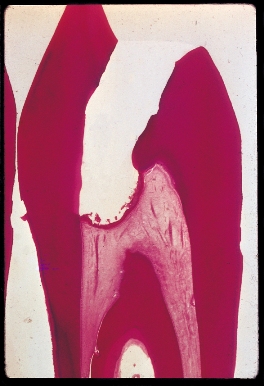

Dentin Bridge Formation

Case 1

This histological section stained with H & E shows new dentin bridge formation two months following pulpal curettage and treatment with Pulpdent Paste.